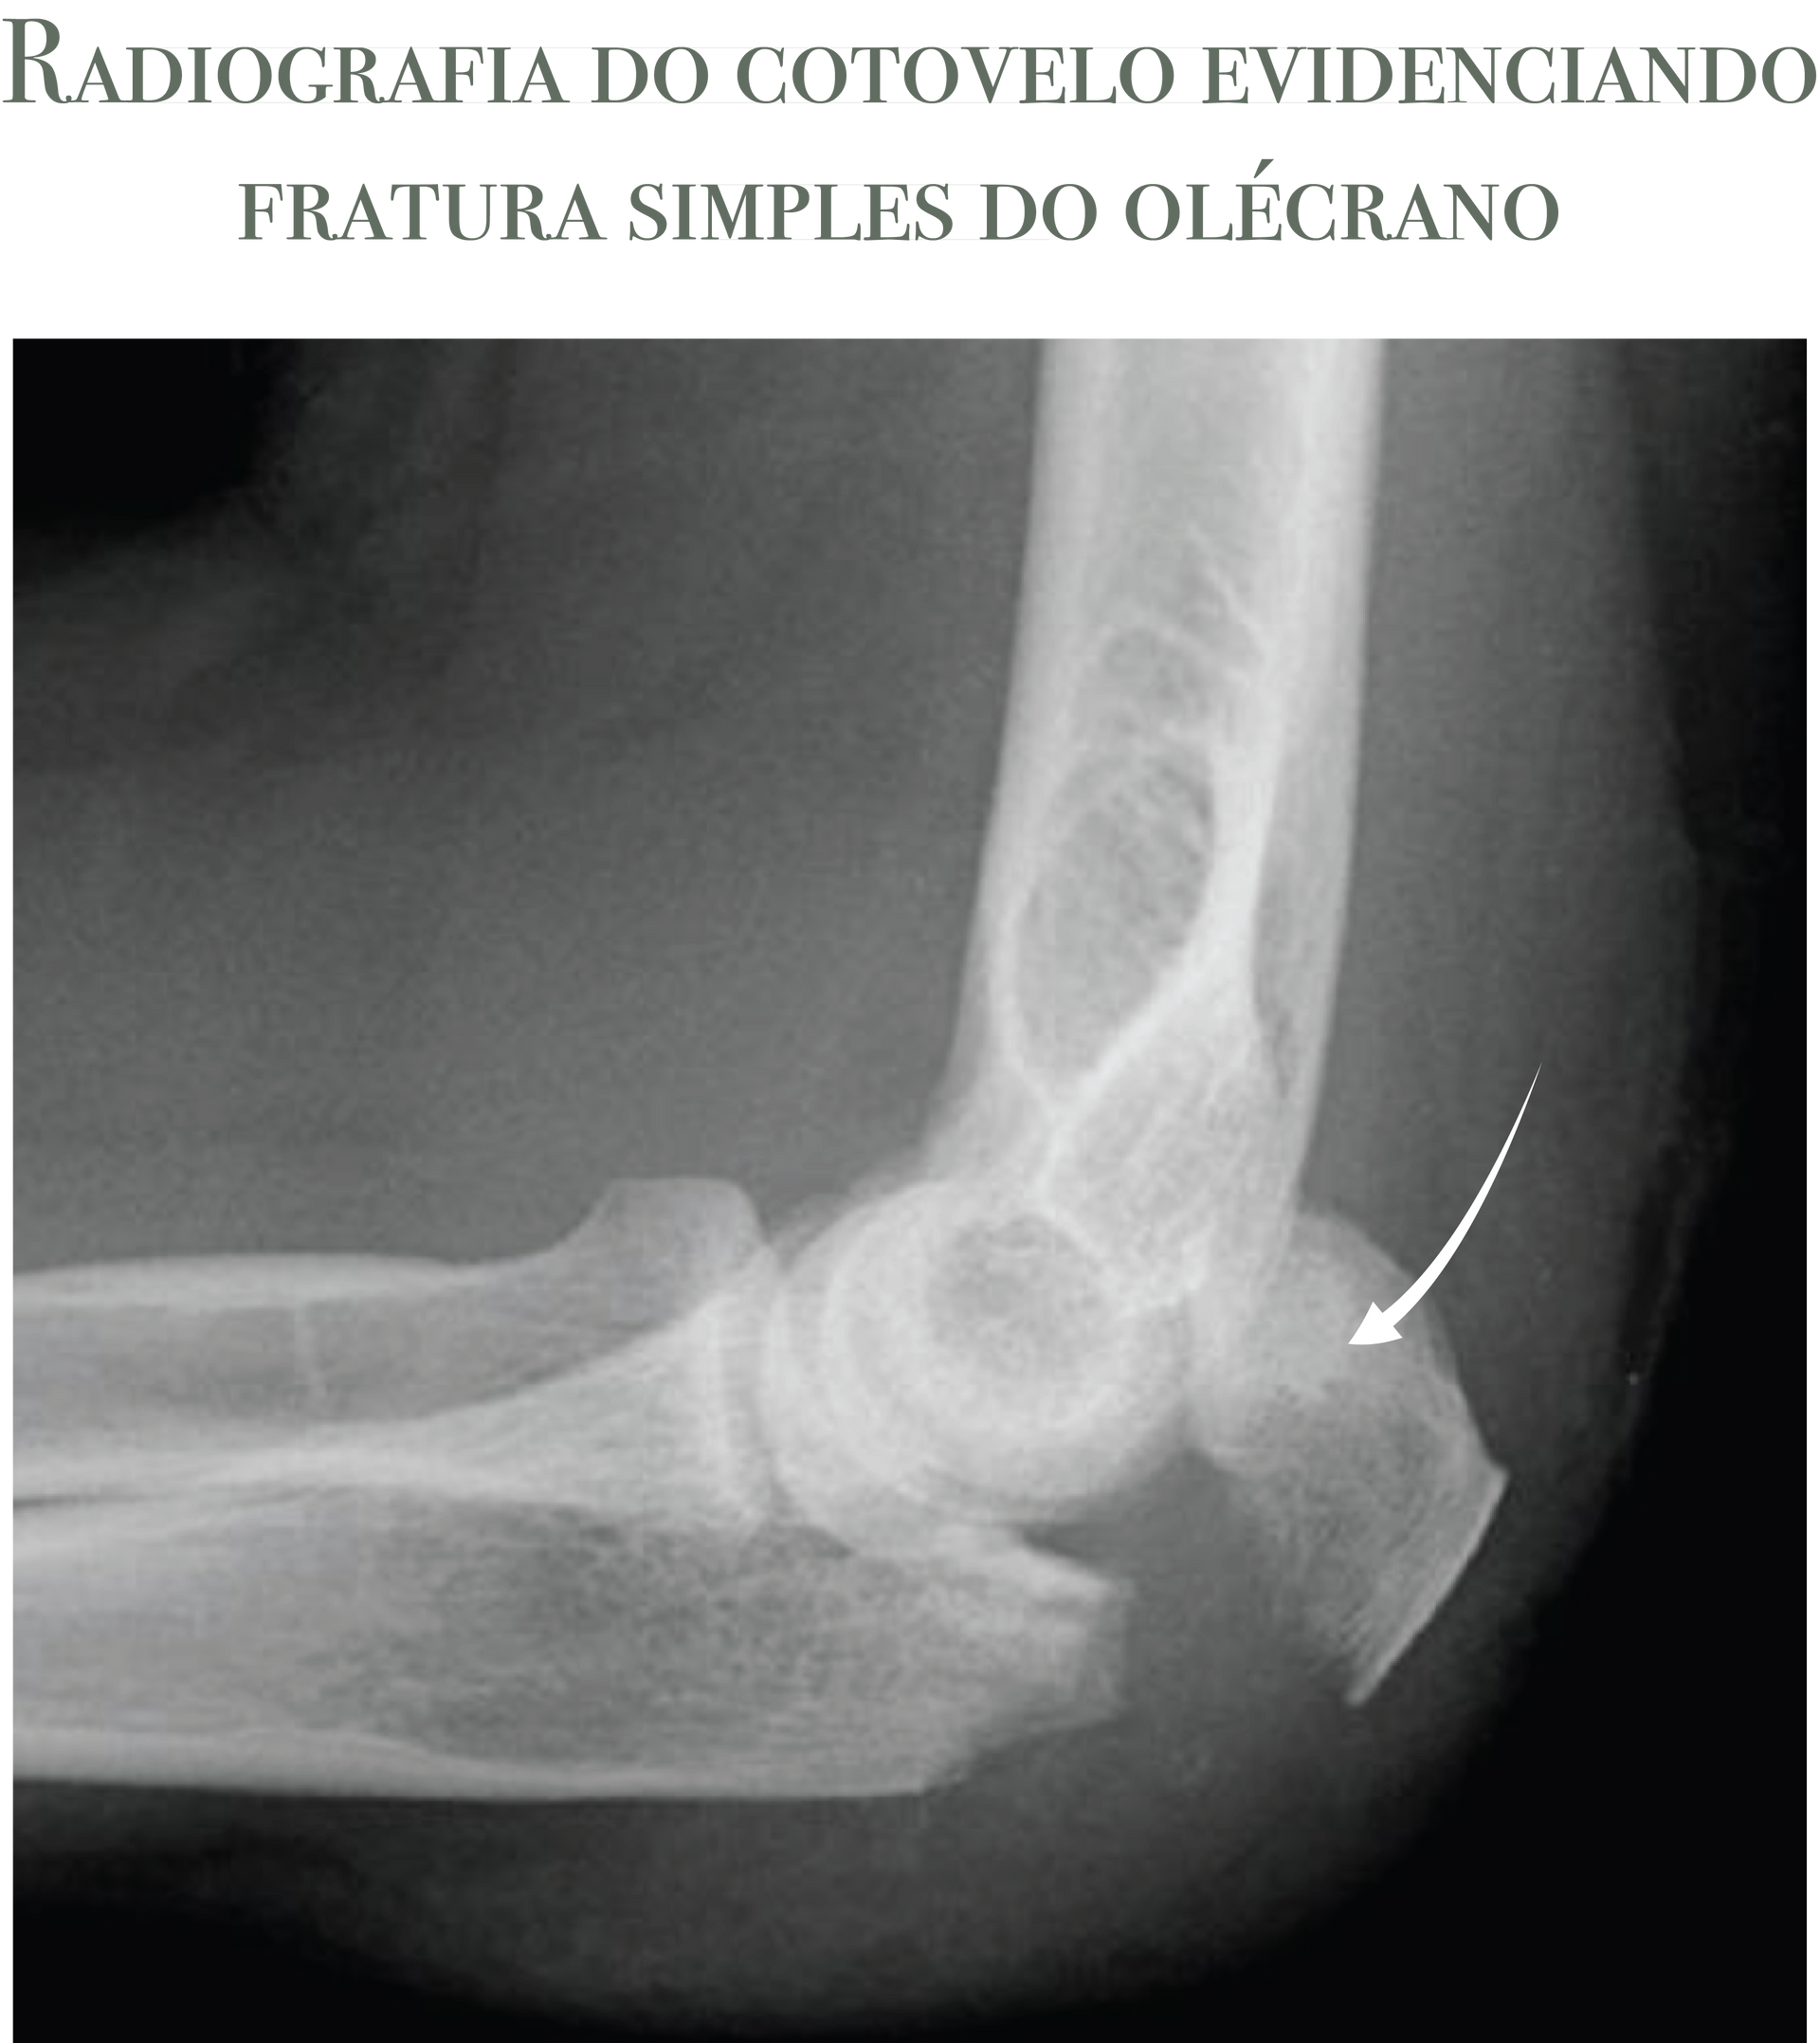

Exames de Imagem

Na imensa maioria dos casos, radiografias em AP e perfil do cotovelo são suficientes para confirmar o diagnóstico e orientar a conduta. A tomografia fica reservada para fraturas mais complexas (muito fragmentadas) ou quando há suspeita de lesões associadas (cabeça do rádio/coronoide) que mudem a estratégia de tratamento.